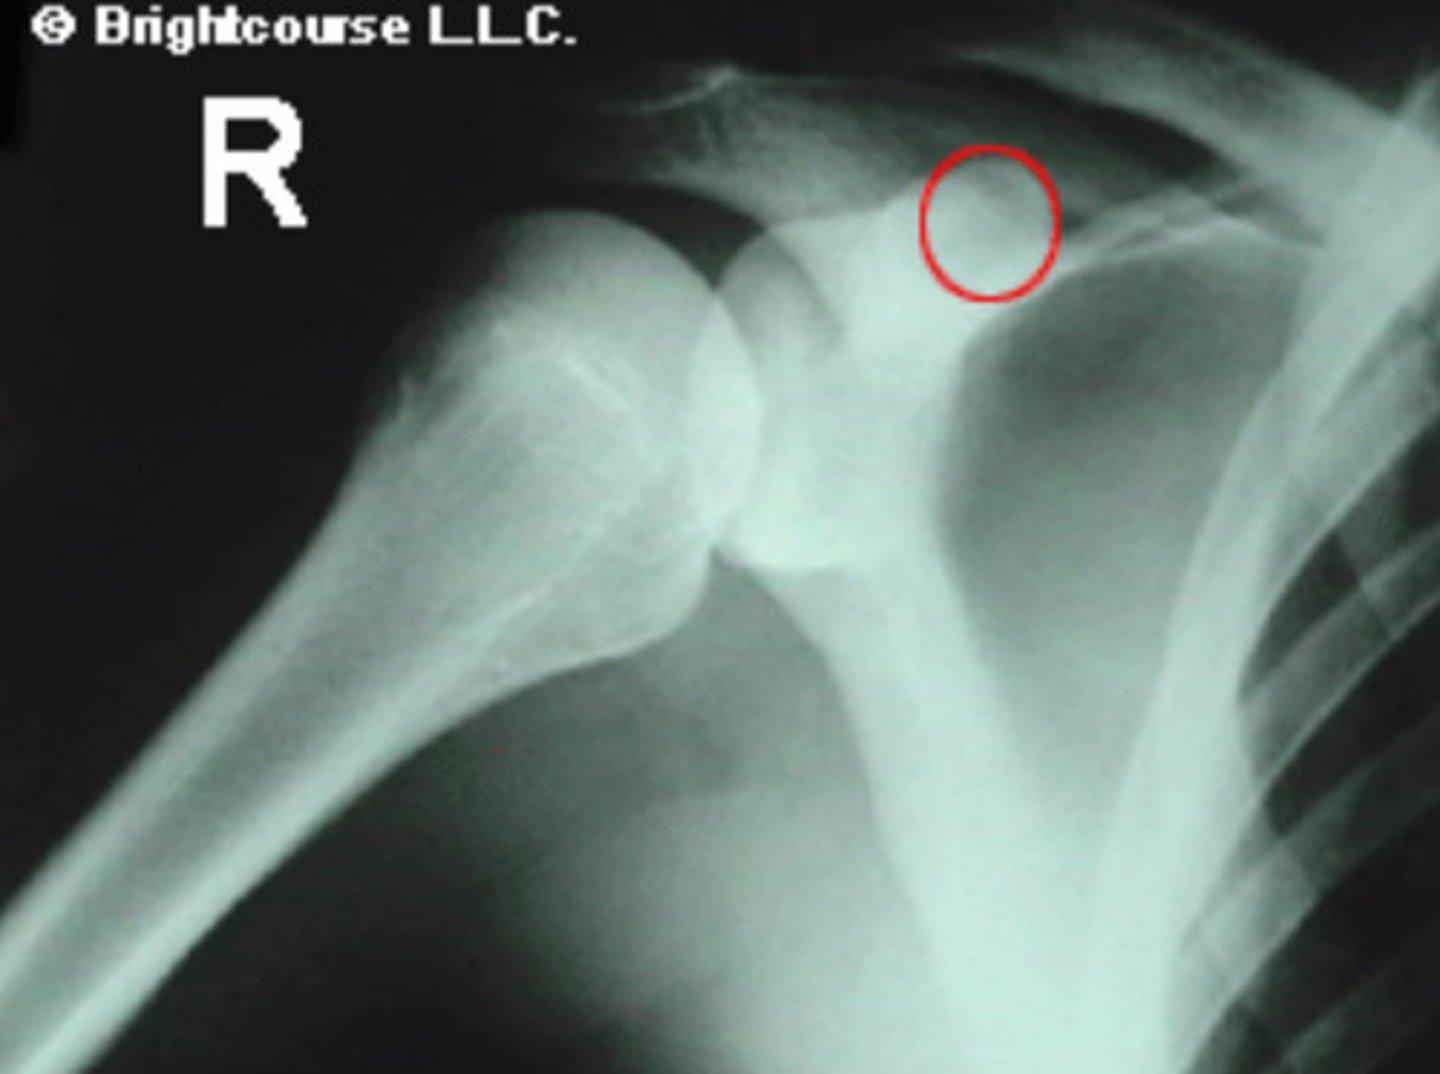

Coracoid process

What is being circled in the image?